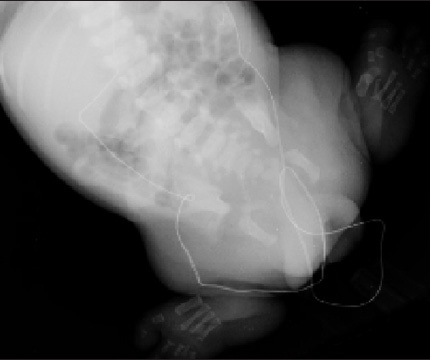

Divina Lopez, MD; Jacob J. Rosenberg, MD

<DIV id=article-content-body> <P><IMG style="MARGIN: 5px; FLOAT: left" alt="Caudal Regression Syndrome"...

A 4-year-old boy presented for further evaluation of persistent right hip pain of 2 months’ duration.